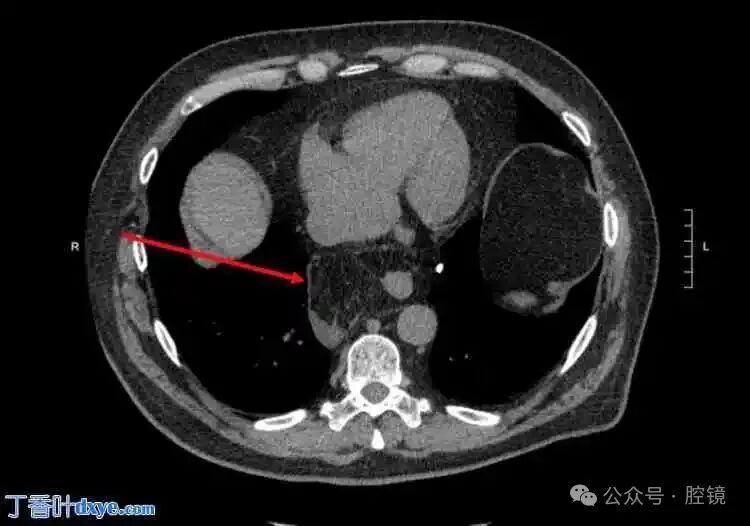

A 65-year-old male presented to the emergency department with a complaint of upper abdominal pain for 48 hours, radiating to the back. His medical history indicated a 5 cm ascendingaortic aneurysm. The patient had no previous surgical history and no significant family history. He exhibited no fever, normal blood pressure, and tachycardia. Physical examination revealed tenderness in the upper abdomen with muscle rigidity, but no rigidity or rebound tenderness. A non-contrast spiral abdominal CT scan showed a soft tissue mass just above the gastroesophageal junction, requiring differential diagnosis with a lipoma or liposarcoma (Figure 1-2). Due to the unclear diagnosis, the physician arranged for a chest MRI. The MRI revealed a large omental hernia through the esophageal hiatus (Figure 3-4), with fluid around the herniated omentum, suggesting strangulation. In the sagittal view of the MRI, the abdominal omentum was seen entering the thoracic cavity (Figure 2-4).Figure 1. Cross-sectional view showing a lipomatous mass behind the heart, with surrounding fluid consistent with strangulated lesions.

Figure 2. Sagittal view of the mass behind the heart.